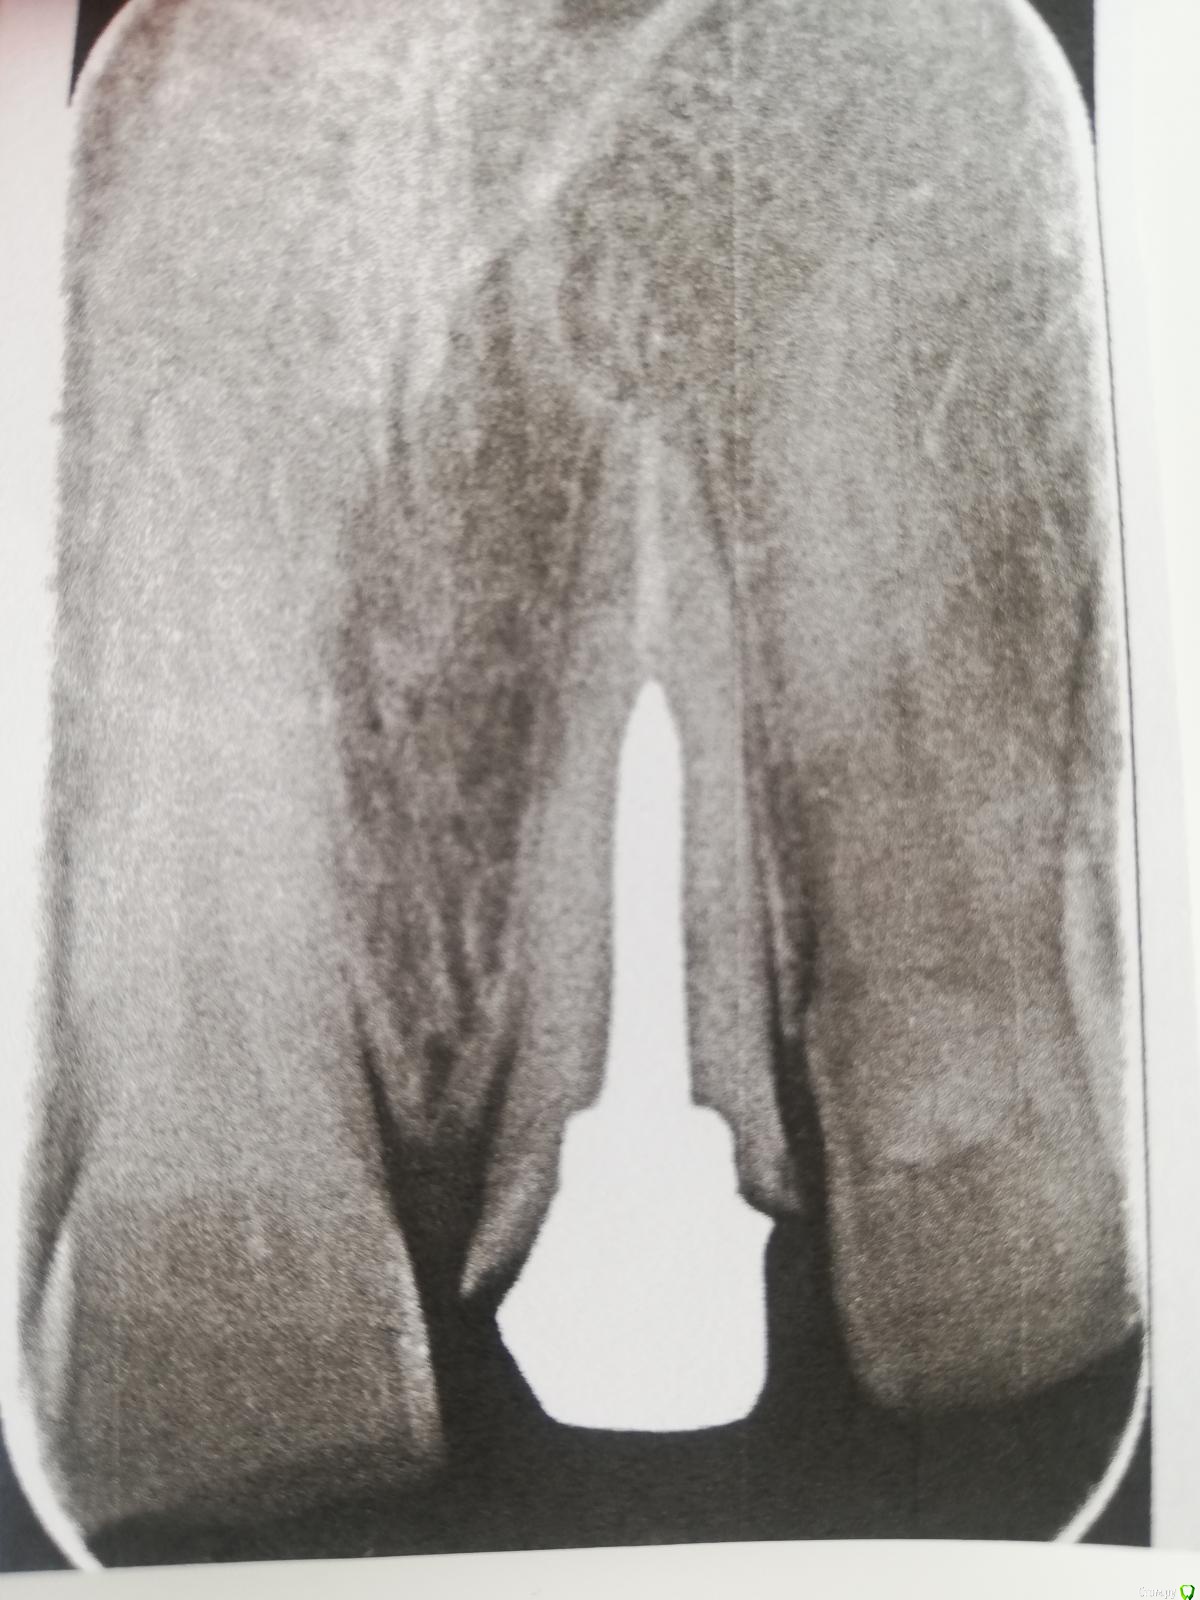

Hadur Опубликовано 2 сентября, 2019 Поделиться Опубликовано 2 сентября, 2019 (изменено) Приветствую. Пришла из лабы вкладка, примерил, щелей визуально нигде нет, вынимал минут 10 обратно - подцепить никак не мог, лампы чтобы прихватить композитом в ортопедии госки у нас нет. Визуально сидело все отлично, по ощущениям тоже. Фото во рту или на модели к сожалению сделать не сообразил сразу. Отправил после фиксации проконтролировать на всякий случай и вижу такую картину. Это такие зазоры или особенность Rg из за разницы пропускаемости металла и тканей зуба? Изменено 2 сентября, 2019 пользователем Hadur Ссылка на комментарий

Doc Опубликовано 2 сентября, 2019 Поделиться Опубликовано 2 сентября, 2019 Приветствую. Пришла из лабы вкладка, примерил, щелей визуально нигде нет, вынимал минут 10 обратно - подцепить никак не мог, лампы чтобы прихватить композитом в ортопедии госки у нас нет. Визуально сидело все отлично, по ощущениям тоже. Фото во рту или на модели к сожалению сделать не сообразил сразу. Отправил после фиксации проконтролировать на всякий случай и вижу такую картину. Это такие зазоры или особенность Rg из за разницы пропускаемости металла и тканей зуба?Она плохо вынималась из-за внутренней части (штифта и разгружающей площадки), наружная слегка подкачала. Но в реальной жизни, при хорошем краевом прилегании коронки, наличии хорошего феррула и высокой точности посадки коронки это не будет иметь сколько-нибудь значимых клинических последствий. Ссылка на комментарий

dentikl Опубликовано 3 сентября, 2019 Поделиться Опубликовано 3 сентября, 2019 А как надо правильно?все правильно,но цемента в краевой зоне не видно,а ф+-контрастный.Снимок это скан кт или снимок рвг? Ссылка на комментарий

Hadur Опубликовано 3 сентября, 2019 Поделиться Опубликовано 3 сентября, 2019 все правильно,но цемента в краевой зоне не видно,а ф+-контрастный.Снимок это скан кт или снимок рвг?Это фотография рвг, напечатаной на бумаге. Ссылка на комментарий